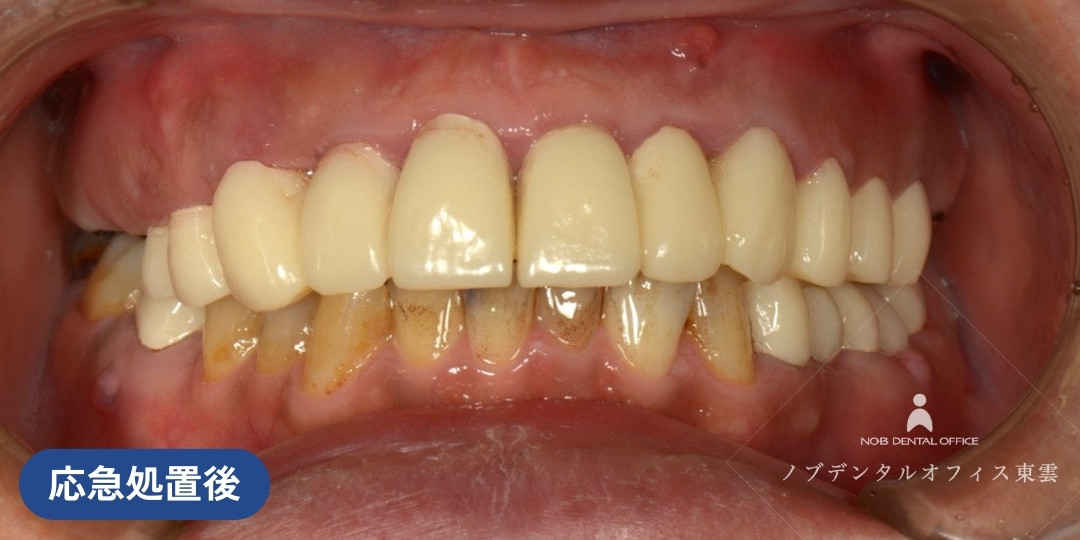

咬合崩壊から機能回復した症例(40代男性の場合)

多数にわたる虫歯・歯周病・かぶせ物の不適合があった方の症例です。

上下の歯が咬み合っておらず、咀嚼機能も低下している状況でした。咬合崩壊(お口全体の噛み合わせのバランスが完全に崩れ、正常に機能しなくなった状態)と診断されました。

初診の時点で「全体的に治療したい」とのことでしたが、まずは応急処置を行い、口腔ドッグによる診察、包括的治療の順に行いました。

まず、初診~応急処置を行いました

「全体的に治療したい」とご来院されました。

審美性と咀嚼機能を確保するため、前歯・臼歯部に仮歯を装着しました。

仮歯により、日常生活での噛み合わせや見た目が一次的に回復しました。

初診のあと、応急処置で仮歯を設置した状態です。